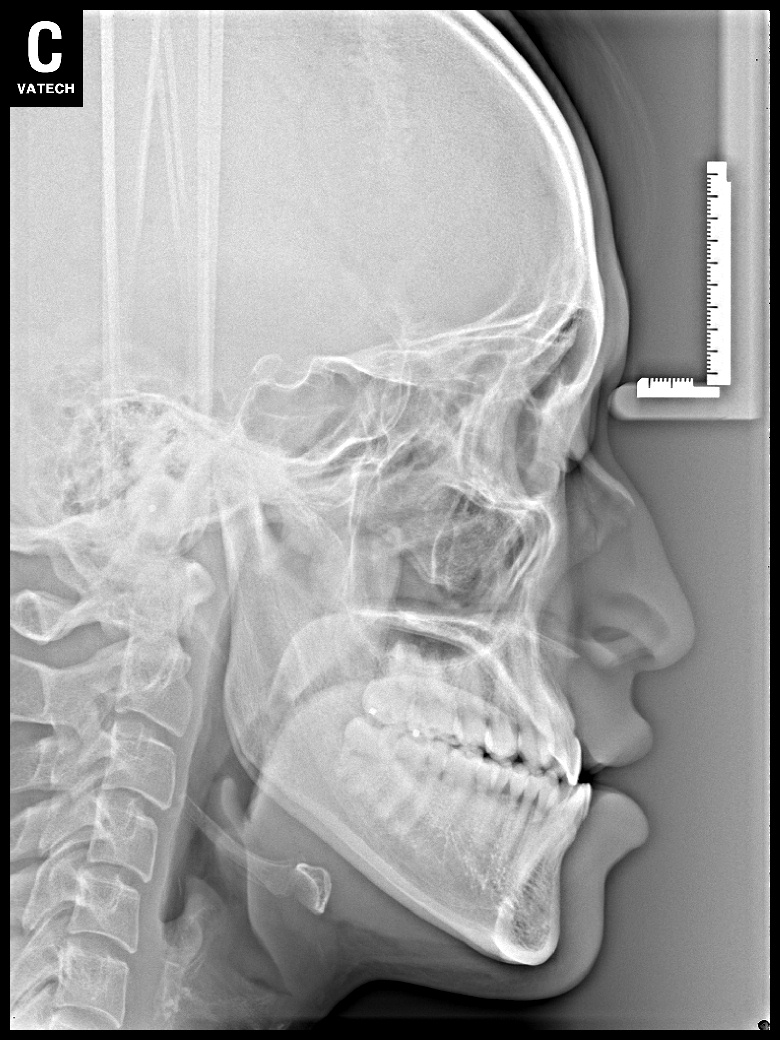

치료 후 사진입니다.